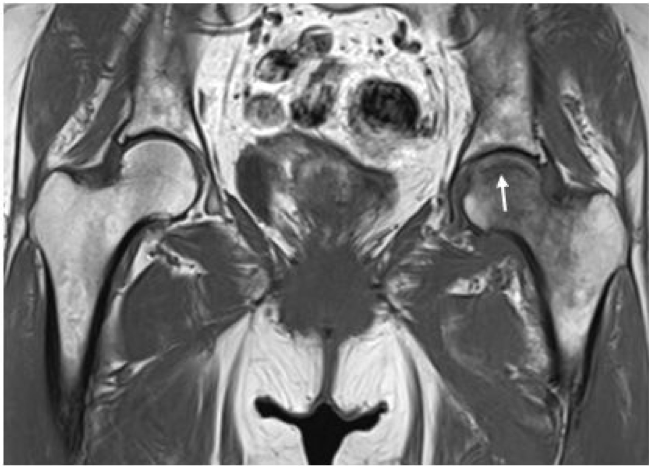

大腿骨頭軟骨下脆弱性骨折の症例

MRI T1強調像(冠状断像)では関節面近傍に中枢に凸の線状低信号像(矢印)や骨頭から頚部に広がる低信号の骨髄浮腫像を認める。

出典

img

1: 著者提供